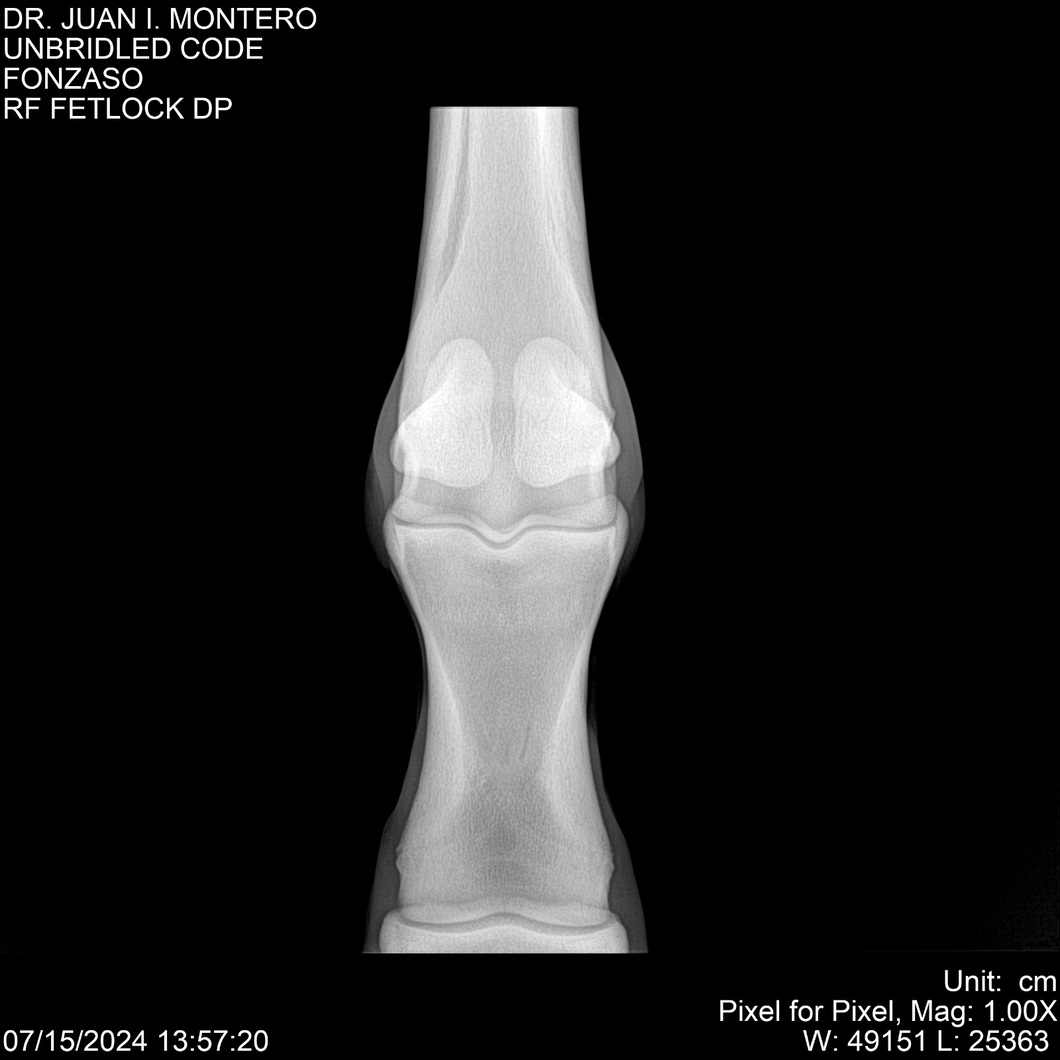

• Empresa: Abelenda N. R., Walter Hugo